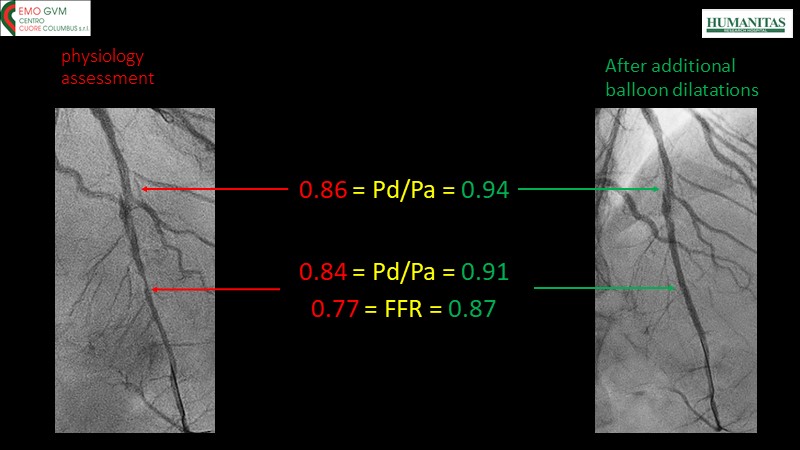

- To know why sirolimus coated balloon is the ideal choice in native vessel disease treatment through a case presentation